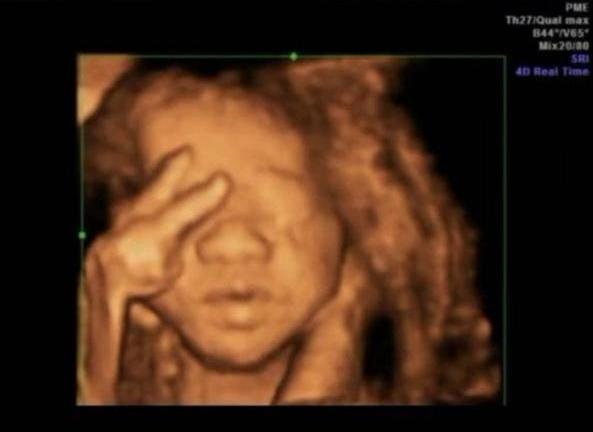

3.“捂鼻胎儿”火了,孕妈做四维彩超遭医生怒斥:真无知

前段时间,30岁的准妈咪小青去医院做四维胎超,当医生看到屏幕画面后,眉头紧锁,她们无法解释胎儿为何会做出如此奇怪的动作。

画面中,胎儿双手捂着鼻子,脸部表情十分痛苦,好似在与某种看不见的东西做抗争。

“我们过去从没见过这个姿势,不过这个姿势肯定不对劲,能和我们讲解下你的生活习惯吗?说不定可以找到答案。”

听到医生的话后,小青表情有些犹豫,不过还是说出了事情的真相。

原来,小青在17岁的时候就已经开始抽烟,每天起码一包烟,连续10年。

结婚后,小青想戒烟,就慢慢减少日均吸烟量,怀孕后更是一根都没碰。

可是,戒烟并不比戒毒轻松太多,小青实在忍不住戒烟的痛苦,就每天偷偷躲外面抽2根烟,抽完再回家。

医生闻言,直接怒斥:

“太无知了!孕妇别说抽2根烟,就连碰都不能碰!”

孕妇抽烟,可能会影响胎儿智商,导致胎儿发育迟缓,甚至可能会引起畸形。

所以,各位没有怀孕的妈妈一定要谨记,千万要戒烟,至少别在怀孕的时候抽烟!